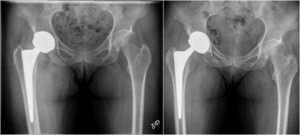

The procedures were performed by five experienced arthroplasty surgeons in our academic institutions. All revision THAs were performed using a posterior approach. The revision was limited to the acetabular component in 26 hips (55%). To retrieve the primary femoral stem, a femoral osteotomy was required in 3 cases (6%). To limit acetabular host bone deficits, the Explant (Zimmer Biomet, Warsaw, Indiana) was used to retrieve the acetabular cup. Allografts were used in 16 cases (34%) to augment acetabular deficits. Press-fit fixation of the acetabular component was obtained by 1 to 2 mm under reaming versus the implant’s outside diameter. Press-fit between the anterior and posterior acetabular rims was achieved in cases where a superior rim deficit was present. One such technique to achieve this was to medialize the implant to increase anterior and posterior rim contact. If superior contact was the preferred option where smaller defects were present; the center of rotation for the hip was elevated by 10 mm. Examples of these principles are demonstrated in Figure 2 and Figure 3.

The mode of fixation of the acetabular implant is widely discussed in the literature. For revision THA, the evidence in the literature suggests cemented fixation has been associated with poor outcomes and a high rate of loosening, whereas excellent outcomes have been documented with press-fit fixation in the revision THA.51–53 Our results also support that in revision THA with limited to moderate bone deficits that do not require structural allograft, adequate press-fit fixation of monobloc acetabular components can be obtained. An adequate press-fit on the anterior and posterior acetabular rims should be sought to optimize fixation. Therefore, if needed, the acetabular component should be medialized before attempting to increase the cup size. In cases of superior bone deficits, a high hip center of up to 10 mm can ensure adequate host bone contact on the superior dome, which is essential for the press-fit stability.54,55 While reaming, surgeons should use increments of 1 mm when approaching the desired diameter to ensure the sphericity of the reamed cavity. If desired, to gain confidence with press-fit only fixation, surgeons could seek adequate fixation with modular components without using screws before switching to press-fit monobloc acetabular components.